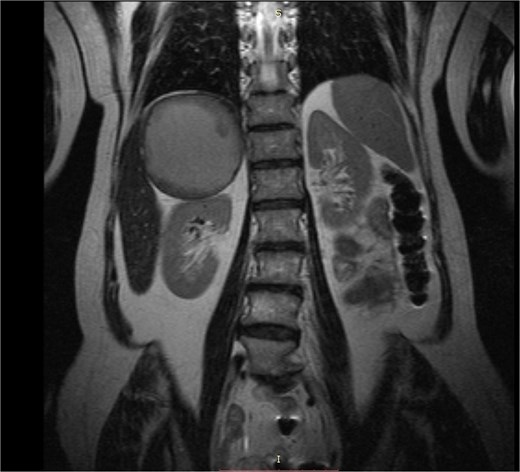

A 60-year-old lady was referred to our department due to a giant right adrenal mass found incidentally on a computed-tomography (CT) scan performed three months earlier for pulmonary infection. The CT scan and magnetic resonance imaging (MRI) (Fig. 1) revealed an 11-centimeter right adrenal pseudocystic mass containing fluid and solid components, with parietal calcifications. Her medical history included anti-hypertensive medication (combination of angiotensin-II blocker and a calcium-channel blocker) and a b-blocker for increased sinus heart rate. From the complete hormonal laboratory only the plasma dopamine levels were increased in two separate samples (190.2 and 196.7 ng/L), raising the clinical suspicion of a dopamine-secreting mass.

MRI caption showing a giant well-circumscribed right adrenal mass with solid components and thick fluid content. The remarkable dimension of the mass can be appreciated if compared to the right kidney.